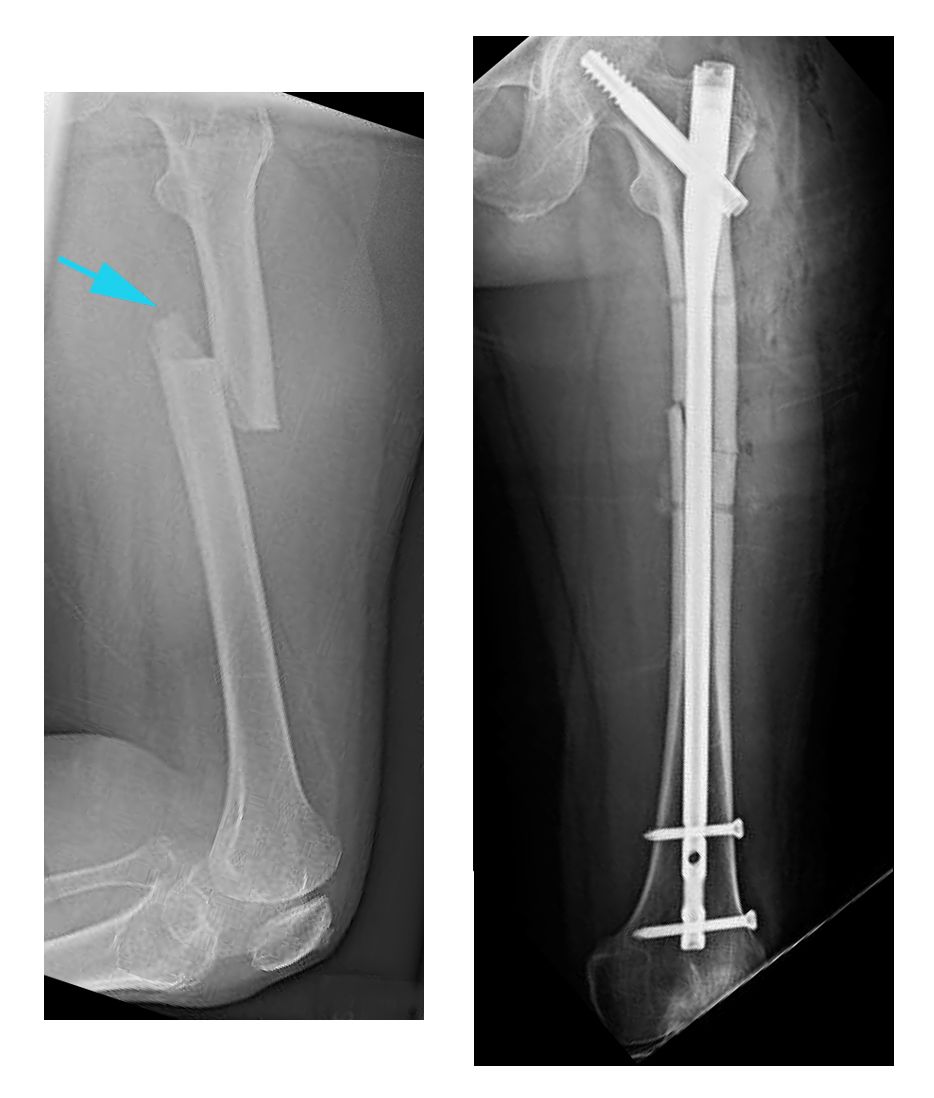

A femoral shaft fracture is a serious injury involving a break in the long, straight part of the thigh bone. Recovery often requires surgery with metal rods, plates, or screws to stabilize the bone. After surgery, physiotherapy plays a crucial role in restoring strength, mobility, and balance while preventing complications such as loss of range of motion, weakness, chronic pain, and loss of independence.

Some fractures occur with little or no trauma and are known as atypical femur fractures. These are rare but may be associated with long-term use of certain osteoporosis medications like bisphosphonates. These medications are very effective for preventing typical fractures but may, after many years, lead to stress-type fractures in the thigh bone.